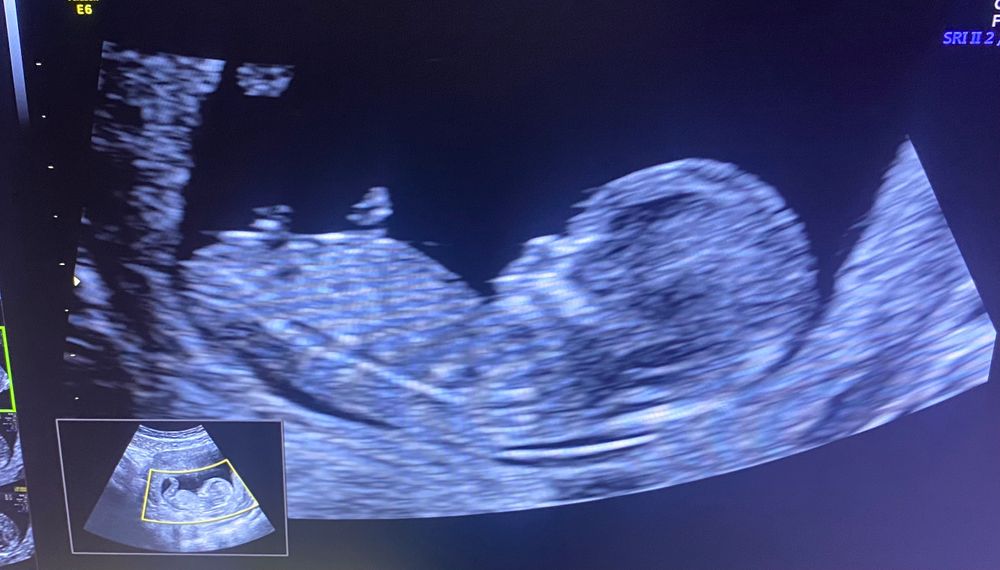

Как думаете кто там сидит? мальчик или девочка?) на узи не сказали и даже не предположили. может по фото будет не понятно) ну а вдруг 😂😂😂

Если бугорок это то, что я вижу, то мальчик)))

Похож на мальчика) сегодня тоже была на скрининге, сказали что пол на таком сроке определить затрудняется)хотя в первые 2 беременности уже на 1 скринигах говорили пол со 100% уверенность и не промахнулись)